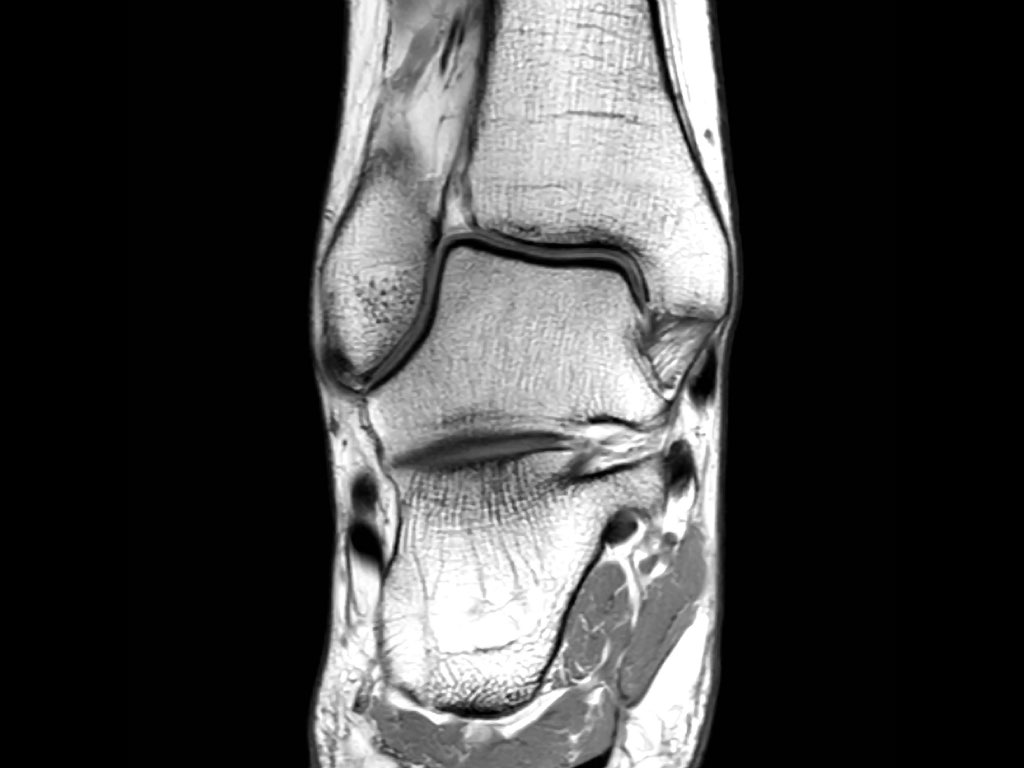

ATFL

Có ba dây chằng ở phía ngoài:

- Dây chằng sên mác trước (anterior talofibular ligament – ATFL)

- Dây chằng gót mác (calcaneofibular ligament – CFL)

- Dây chằng sên mác sau (posterior talofibular ligament – PTFL).

Dây chằng ATFL chạy từ mắt cá ngoài ra phía trước đến bờ ngoài của xương sên.

Dây chằng này có hướng nằm ngang và được quan sát rõ nhất trên ảnh cắt ngang.

Đây là dây chằng bị tổn thương thường gặp nhất ở cổ chân và cũng là dây chằng đầu tiên bị tổn thương ở phía ngoài.

Điều này có nghĩa là khi dây chằng CFL hoặc PTFL bị tổn thương, rất có khả năng dây chằng ATFL cũng đã bị tổn thương.

Cuộn qua các ảnh cắt vành.

Bạn có thể phóng to ảnh bằng cách nhấp vào.

Đây là hình ảnh của ba bệnh nhân có tổn thương dây chằng ATFL.

Bệnh nhân bên trái có phù nề nhẹ xung quanh dây chằng ATFL, trong khi bản thân dây chằng trông bình thường.

Đây có thể là căng dây chằng mức độ nhẹ (độ 1).

Thường được nhận thấy rõ nhất trên ảnh có kỹ thuật ức chế mỡ (fatsat).

Bệnh nhân ở giữa có dày lên và rối loạn cấu trúc, biểu hiện của rách một phần (độ 2).

Bệnh nhân bên phải có rách toàn bộ chiều dày (độ 3).